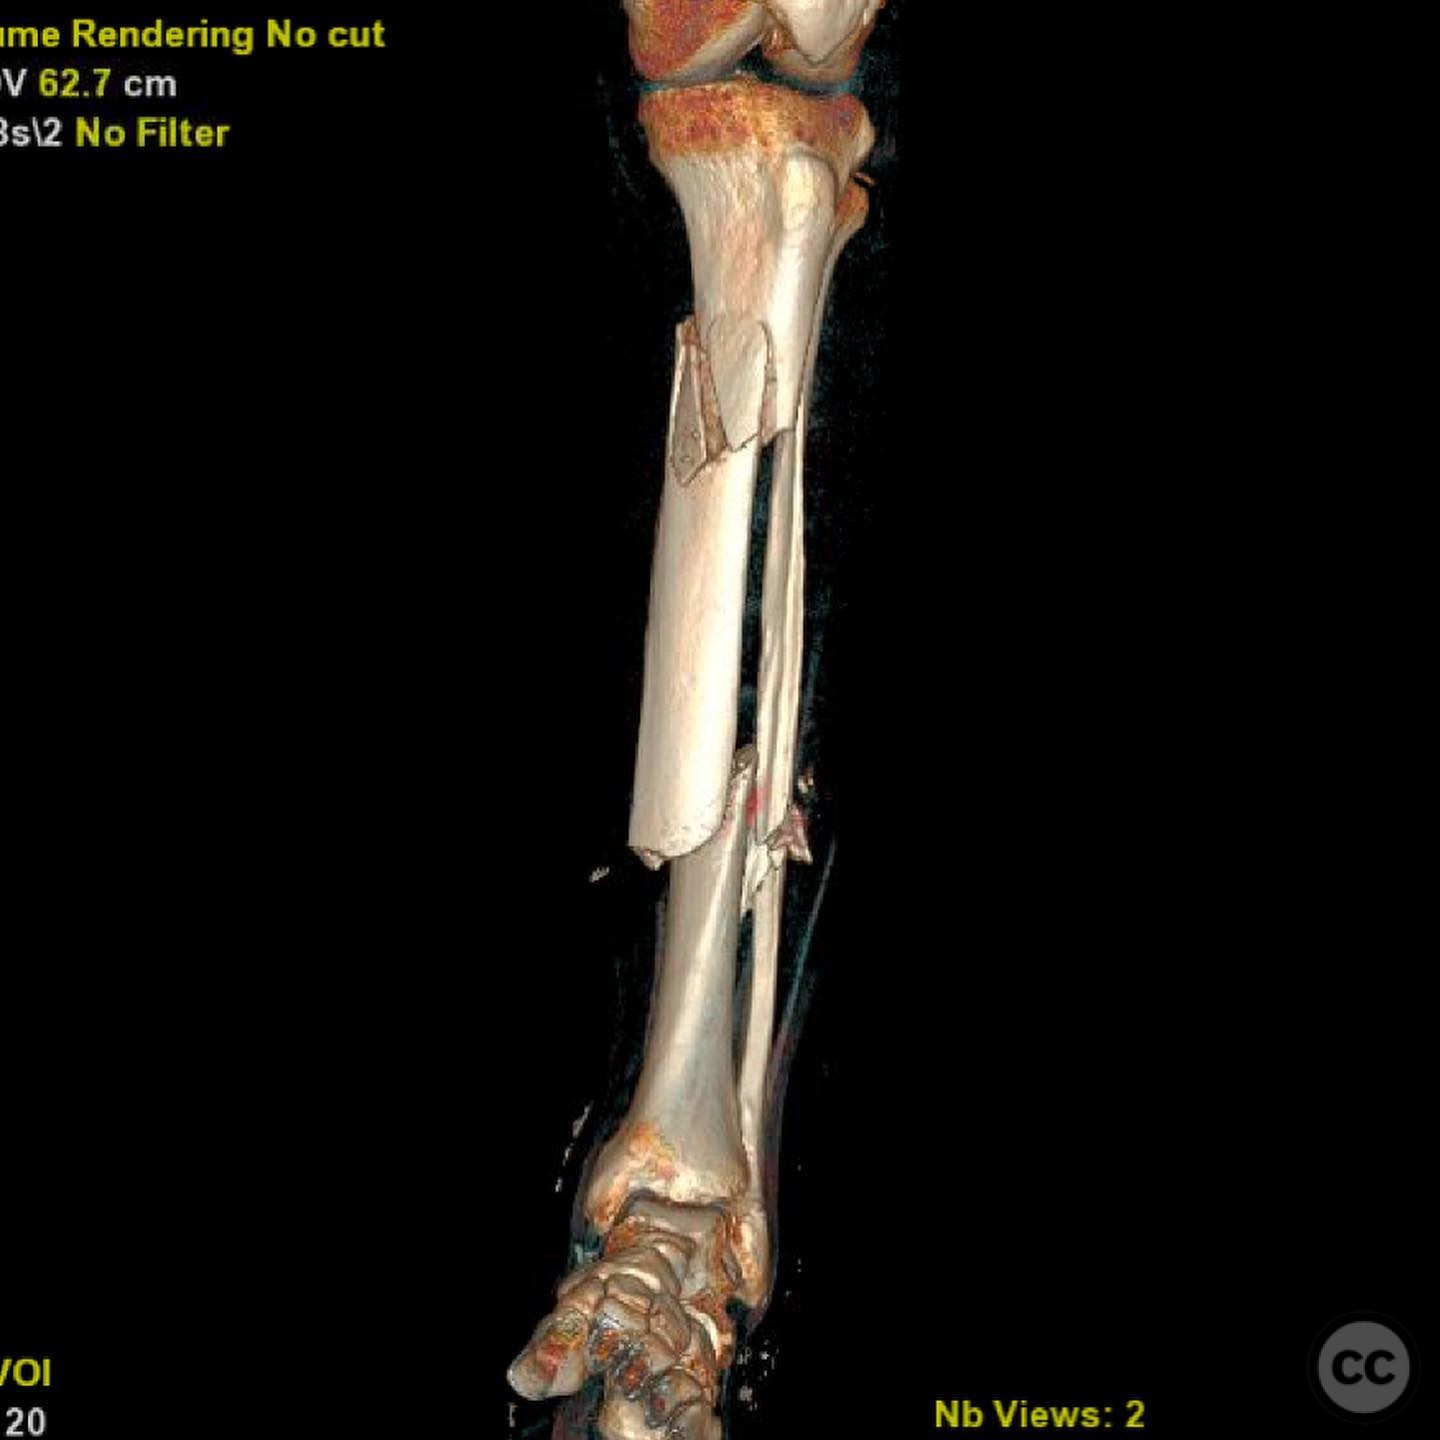

Clinical and radiological findings:  A 44-year-old male cyclist was involved in a collision with a car, resulting in open fractures of the distal femur and segmental tibia. The femoral fracture presented with a 4 cm transverse wound on the anterior aspect, while the tibial fracture had a 2 cm anterolateral wound at the distal site. There were no associated head, chest, or abdominal injuries, and compartment syndrome was not present. Vascular examination was unremarkable.

Planning remarks:  The preoperative plan involved initial debridement and irrigation of both open fractures. The tibia was prioritized for intramedullary nailing, followed by spanning external fixation of the distal femur. Definitive fixation of the distal femur was planned for two days post-initial stabilization.

Anatomical surgical approach:  For the tibia, a longitudinal incision was made to access the proximal tibial start site for intramedullary nailing. Percutaneous clamps were utilized for reduction, supplemented by blocking screws as needed. For the distal femur, an external fixator was applied initially, followed by an in situ lateral approach for plating after reduction was achieved.